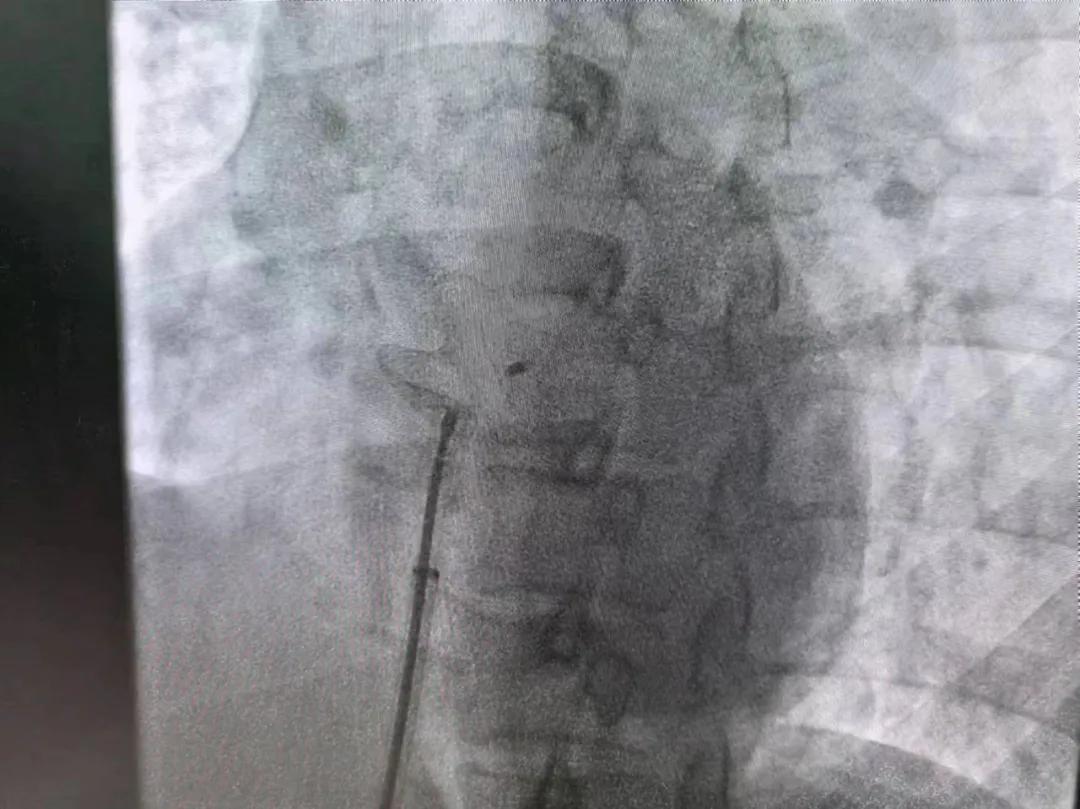

繼3月14日市二院成功開展首例卵圓孔未閉介入封堵術(shù)之后,3月21日上午,市二院院長(zhǎng)王瑾及心血管內(nèi)科主任李慧新帶領(lǐng)心血管內(nèi)科介入團(tuán)隊(duì),再次成功為患者實(shí)施“經(jīng)皮房間隔缺損封堵術(shù)”,手術(shù)過程順利。該例病人的成功手術(shù)及康復(fù),標(biāo)志著市二院心血管內(nèi)科在結(jié)構(gòu)性心臟病介入診療中再次達(dá)到了新高度。

患者為中年女性,41歲,近2年一直反復(fù)出現(xiàn)頭暈、頭痛,曾先后在多家醫(yī)院就診。近期患者癥狀加重,出現(xiàn)活動(dòng)后氣喘合并胸悶癥狀,來到心血管內(nèi)科就診。經(jīng)心臟彩超檢查顯示:患者房間隔下段連續(xù)性中斷,缺損直徑達(dá)到了13mm,肺動(dòng)脈壓已經(jīng)輕度增高,確診為房間隔缺損。

于是,院長(zhǎng)王瑾會(huì)診后,詳細(xì)詢問患者病史,認(rèn)真分析臨床癥候群并準(zhǔn)確診斷,耐心做好患者及家屬病情告知和充分溝通。經(jīng)過完善的術(shù)前評(píng)估及準(zhǔn)備,心血管內(nèi)科介入團(tuán)隊(duì)成功為患者實(shí)施“經(jīng)皮房間隔缺損封堵術(shù)”,手術(shù)過程順利。近日,患者已順利康復(fù)出院。 (尹紅婭 潘長(zhǎng)林)